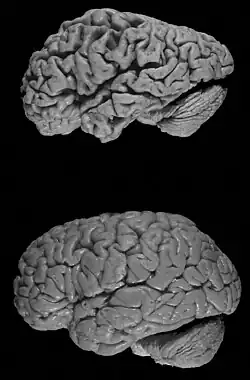

Im Krankheitsverlauf nimmt die Hirnmasse durch das Absterben von Neuronen vermehrt ab; man spricht dabei von einer Hirnatrophie. Außerdem wird der Botenstoff Acetylcholin nicht mehr in ausreichenden Mengen produziert (unter anderem durch Verminderung des im Nucleus basalis vorkommenden Enzyms Cholinacetyltransferase, das die Zusammensetzung von Acetyl-CoA und Cholin katalysiert), was zu einer allgemeinen Leistungsschwächung des Gehirns führt.